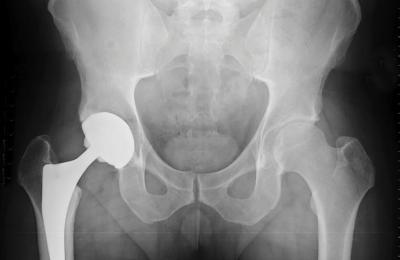

04.08.2020 Смяната на тазобедрената става е операция, при която се отстраняват увредените или заболели части от тазобедрената става и се заменят с нови - изкуствени. Самата операция се нарича артропластика.... |